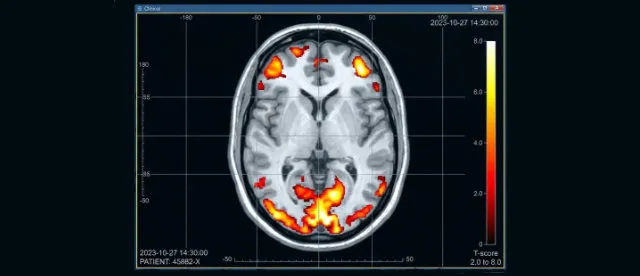

Immagini colorate

Per oltre due decenni, ci è stata raccontata una storia affascinante: la psichiatria era finalmente diventata una "vera scienza" grazie alla risonanza magnetica funzionale (fMRI). Quelle immagini colorate del cervello, con macchie luminose che si accendono in risposta a emozioni o pensieri, sono state spacciate come prova tangibile della causa cerebrale dei cosiddetti disturbi mentali, come depressione, schizofrenia e disturbi dell’umore.

L'intera "scienza" delle neuroimmagini si basa su un presupposto che davamo per scontato: se una parte del cervello lavora di più, ha bisogno di più ossigeno, quindi il flusso sanguigno aumenta. La macchina (fMRI) rileva questo afflusso di sangue (chiamato segnale BOLD) e noi interpretiamo quella "macchia colorata" come un segno di aumentata attività neuronale.

Lo studio della TUM, guidato dalla dottoressa Samira Epp e dal professor Valentin Riedl, ha scoperto che nel 40% dei casi questo presupposto è falso. I ricercatori hanno utilizzato una tecnica innovativa per misurare l'effettivo consumo di ossigeno e hanno scoperto realtà paradossali:

1. In molte aree, il segnale fMRI aumentava mentre l'attività cerebrale reale diminuiva.

2. In altre zone, i neuroni lavoravano freneticamente, ma il segnale fMRI scendeva.

Si è scoperto infatti che molte regioni cerebrali soddisfano l'aumento della domanda energetica non incrementando il flusso sanguigno come previsto, ma estraendo l'ossigeno in modo più efficiente dalla loro attuale disponibilità di sangue.

"Questo contraddice l'assunto di lunga data su cui si basano decine di migliaia di studi in tutto il mondo", ha spiegato la dottoressa Epp. Per la psichiatria, che ha usato queste mappe per "dimostrare" che i disturbi mentali sono squilibri biologici visibili, si tratta di un disastro epocale. Se il segnale può significare l'esatto opposto di ciò che pensavamo, allora migliaia di conclusioni “scientifiche” sulla depressione o sulla schizofrenia potrebbero dover essere ribaltate.